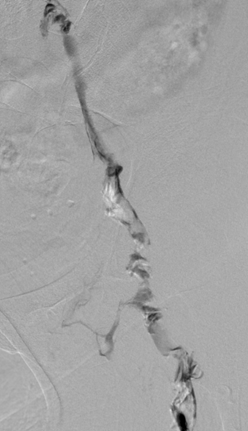

Acceso poplíteo; vista de posición decúbito prono de un trombo oclusivo agudo en la vena poplítea izquierda y en la vena femoral.

Acceso poplíteo; vista de posición decúbito prono de un trombo oclusivo agudo en la vena femoral izquierda y en las venas ilíacas.